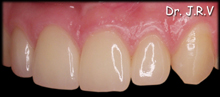

| Foto 4A.- Dientes 12 y 22 conoides. Vista frontal |

Foto 4B.- Carillas de porcelana en 11, 12, 21 y 22. Vista Frontal. |